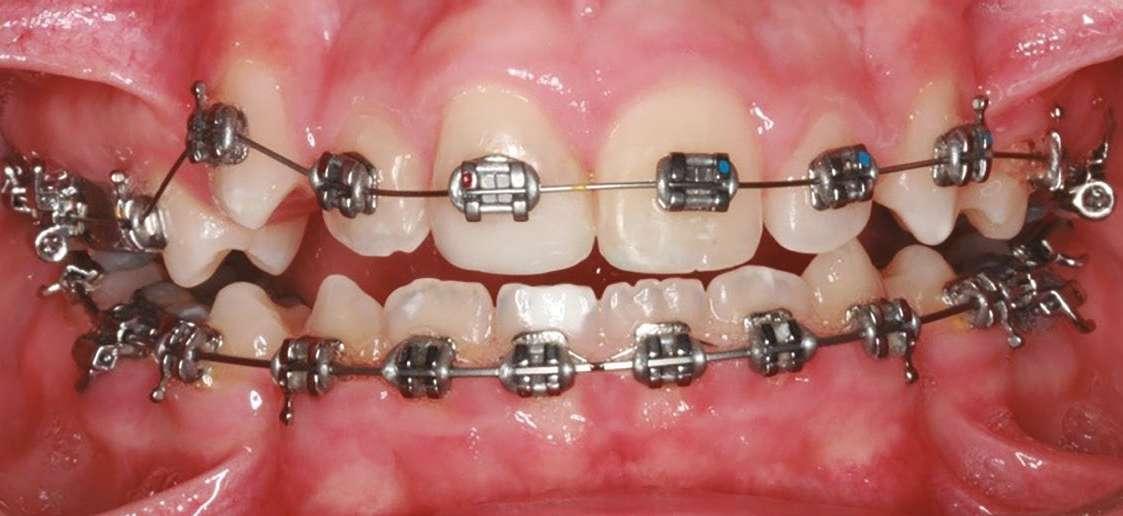

Imágenes 1 y 2. Caso de paciente de 8 años, sexo masculino. En tratamiento se pueden ver los cambios estructurales y oclusales al modificar las funciones de respiración y posición lingual con sistema miofuncional, en 5 meses.

1 2